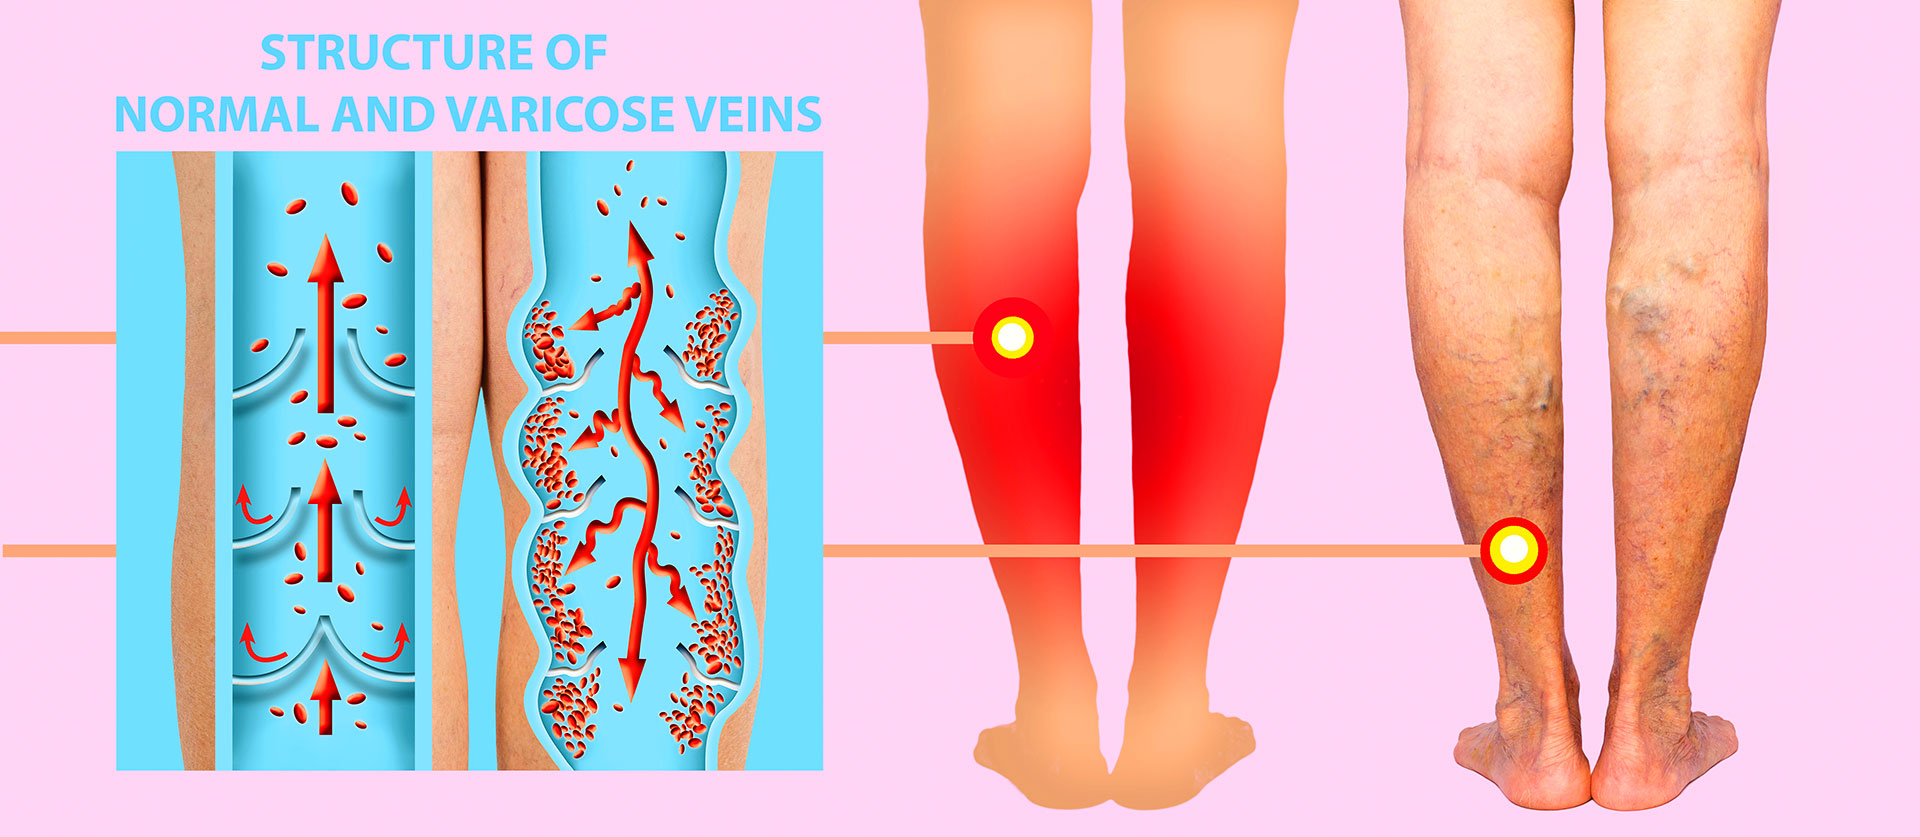

To understand why teachers are so vulnerable, it helps to first understand how leg veins actually work. Unlike arteries, which rely on the heart's pumping force to move blood, veins in the legs must push blood upward against gravity, relying on a series of one-way valves and the contraction of surrounding calf muscles.

When you walk, your calf muscles compress the veins with each step, propelling blood upward toward the heart. When you stand still for long periods, however, that muscle pump becomes entirely idle. As a direct consequence, blood begins to pool in the lower leg veins, steadily increasing internal pressure on the vessel walls with every passing hour.

Over time, this repeated pooling gradually weakens vein walls and stretches the delicate valves that keep blood flowing in one direction. Once those valves fail, a condition known as venous reflux, blood flows backward and consequently pools even more aggressively. As a result, the vessels enlarge, twist, and bulge visibly under the skin, causing the pain and discomfort most people recognize as varicose veins.